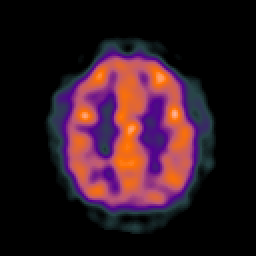

AIDS dementia: overlay -- Slice #13

[Home][Help][Clinical][Tour 1] Slice 13